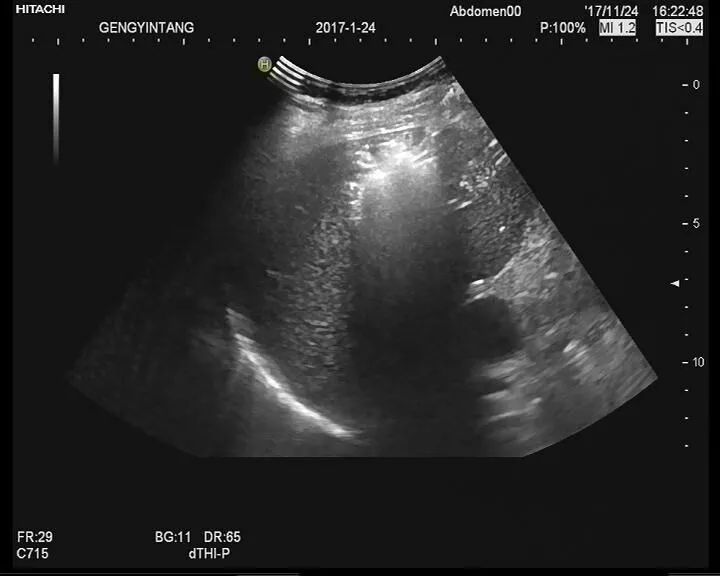

AEP发病之初,胸片可能仅有轻微的网状影或磨玻璃影,常可见Kerley B线。随着疾病进展,可出现双肺弥漫性混合的磨玻璃影和网状影。就诊时也可见单独的磨玻璃影(约25%的病例)或网状影(约25%)。AEP的阴影呈弥漫性分布,而CEP的阴影通常局限于肺外周。少量胸腔积液很常见(见于多达70%的患者),常为双侧。